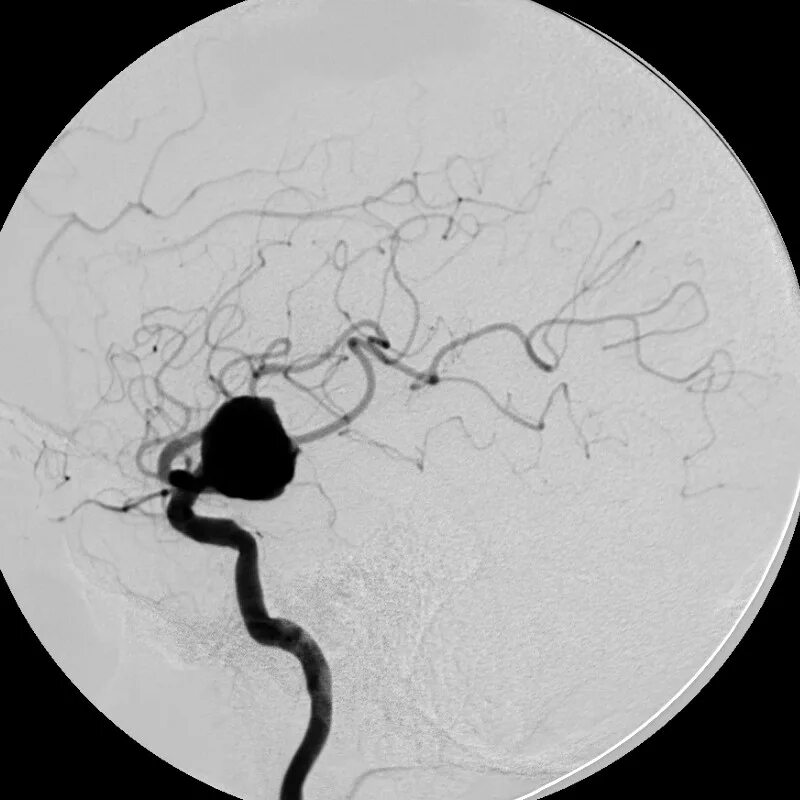

Аневризма головного мозга на кт